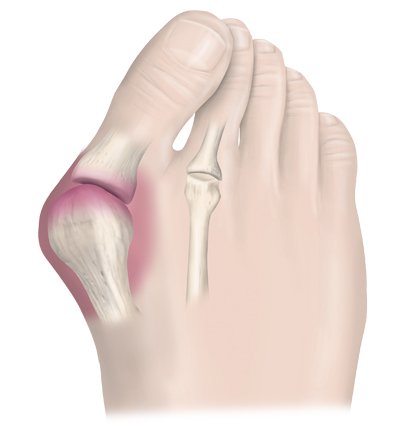

Medicinens ABC Mortons metatarsalgi, hallux valgus och hallux rigidus